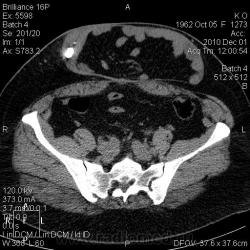

Свищи передней брюшной стенки. КТ.

Женщина 1962 г.р. В анамнезе псевдокиста поджелудочной железы, прооперирована около 6 мес назад. Фистуло-КТ. И красавица грыжа.